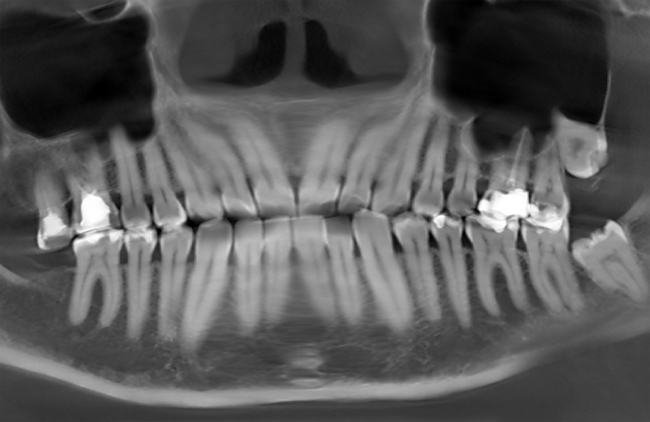

Визначає може за зуба боліти вухо стоматолог. Підтверджує запалення і виникає в наслідок симптом, що віддає в область вушної раковини рентген-знімок щелепи, починаючи з ікла і до останньої одиниці.

- середнє або глибоке руйнування жувальних елементів, починаючи з третього від середини викликає відчуття, що болить зуб заклало вухо;

- складний, тривалий поява вже сформувався останнього елемента, вісімки, особливо при неправильному його розташування;

- запалення нервів, розташованих усередині каналів, при цьому кістками чином відчувається, що болить зуб і вухо одночасно, неначе щось здавило;

- поява набряку ясен з-за хронічного утворення кісти.